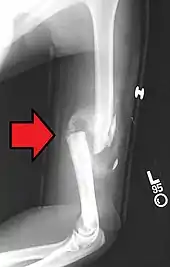

Fraturas

Nos locais de fratura óssea ocorre hemorragia, pela lesão dos vasos sanguíneos, destruição da matriz e morte de células ósseas.

Macrófagos removem o coágulo sanguíneo, restos de células e restos da matriz para que se possa começar o reparo da fratura. O periósteo e o endósteo próximos à área de fratura respondem com uma intensa proliferação, formando um tecido muito rico em células osteoprogenitoras que constitui um colar em torno da fratura e penetra entre as extremidades ósseas rompidas. Esse processo se desenvolve de modo a aparecer um calo ósseo após algum tempo.

As trações e pressões exercidas sobre o osso durante a reparação da fratura, e após o retorno do paciente a suas atividades normais, causam a remodelação do calo ósseo e sua completa substituição por tecido ósseo lamelar. Se essas trações e pressões forem idênticas às exercidas sobre o osso antes da fratura, a estrutura do osso volta a ser a mesma que existia anteriormente; é exatamente essa uma das principais funções das sessões de fisioterapia recomendada para pacientes que sofreram fraturas. Ao contrário dos outros tecidos conjuntivos, o tecido ósseo, apesar de ser duro, repara-se sem a formação de cicatriz.